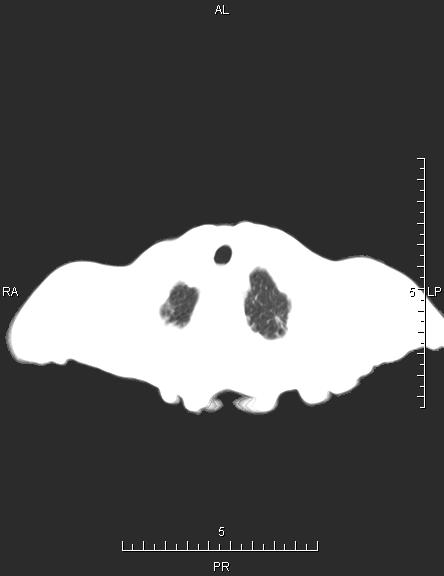

CT51434:胸部CT

女,82岁,咳嗽、咳痰10余天,憋气3天。

两肺纹理增多,两肺散在少许索条影,右下肺可见斑片结节影,斑片影内见支气管气相,相应支气管狭窄,同侧胸腔积液,左侧甲状腺见低密度影,考虑:右下肺占位伴阻塞性炎症,两肺间质性炎症,左侧甲状腺占位--腺瘤可能。

1、考虑右肺下叶占位性病变伴阻塞性肺炎,建议支气管镜检查。

2、右侧胸腔积液。

3、两肺间质性改变。